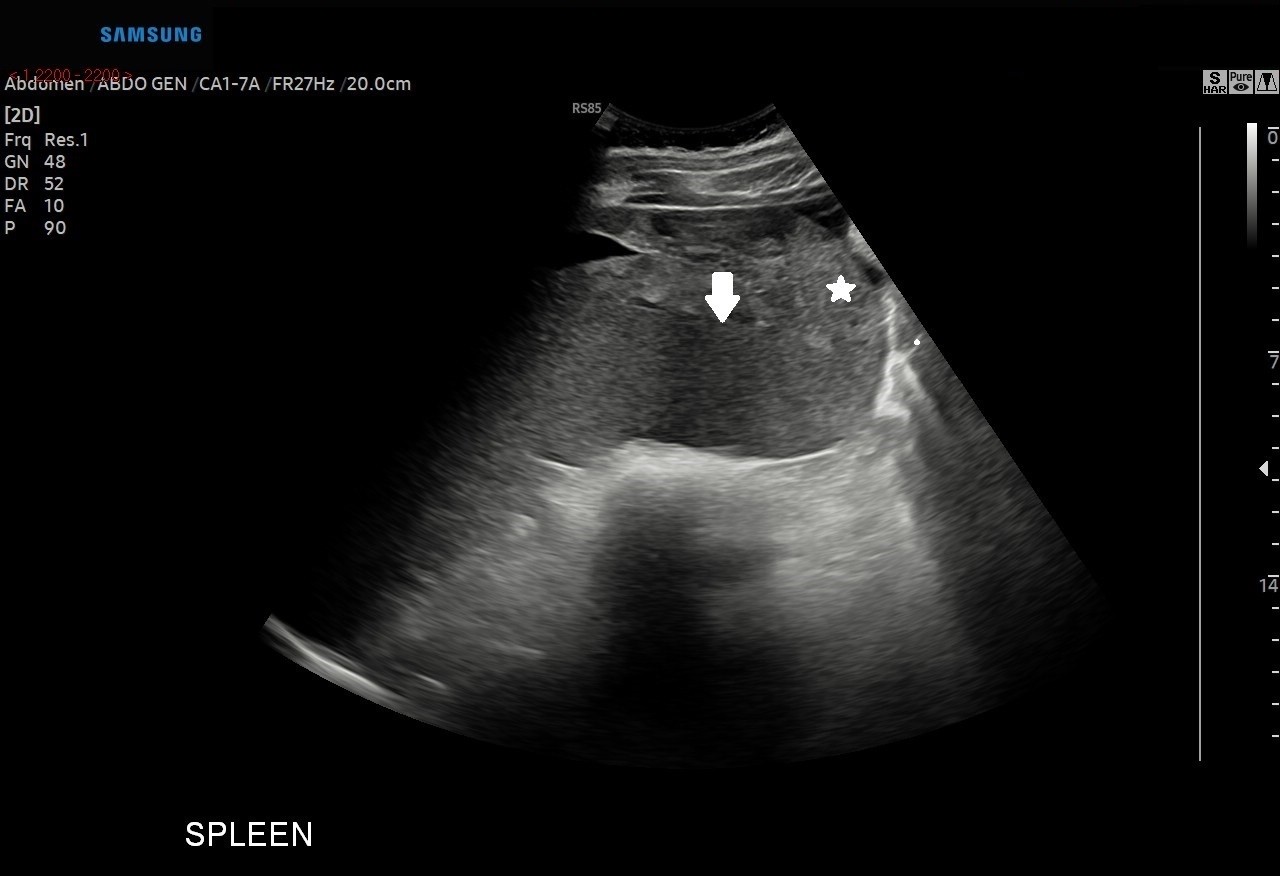

A heterogenous area with a small area of central fluid left subphrenic space surrounding/indistinct from the superior spleen was identified with no colour doppler flow.

Figure 2, 3 and 4 above; Heterogeneous area(star) with a small area of central fluid in the left subphrenic space surrounding and indistinct from the spleen (arrow)